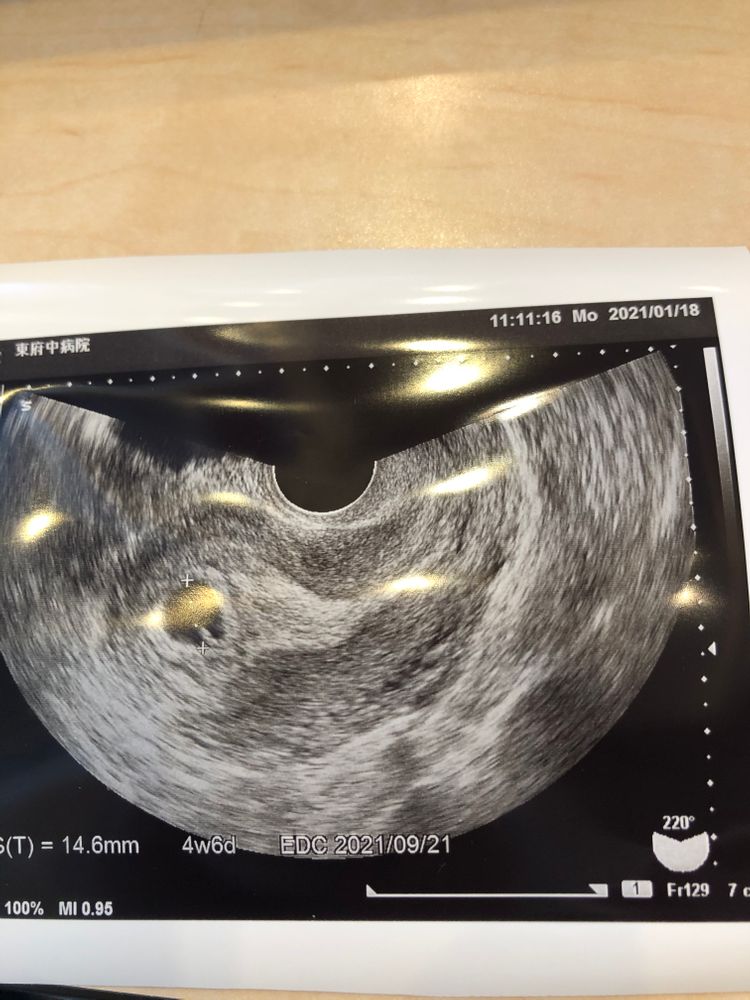

Сходила сегодня на узи, за неделю плодное яйцо выросло практически в 5 раз и составляет практически 15 мм, было 3 мм неделю неделю назад , желточный мешочек есть, а эмбриона не видно . Сходили придти на повторное узи через неделю . Я верю в своего малыша и в то, что на все Воля Божья. ( и мне кажется , что внутри плодного яйца все-таки что -то есть).